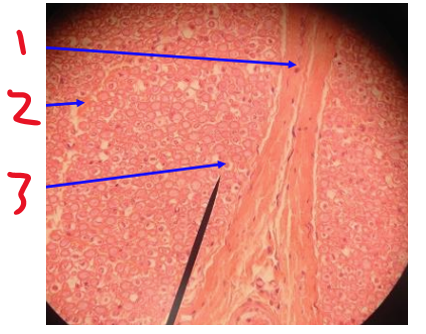

Name structure 1

glial cells

Name structure 2

cell body OR soma